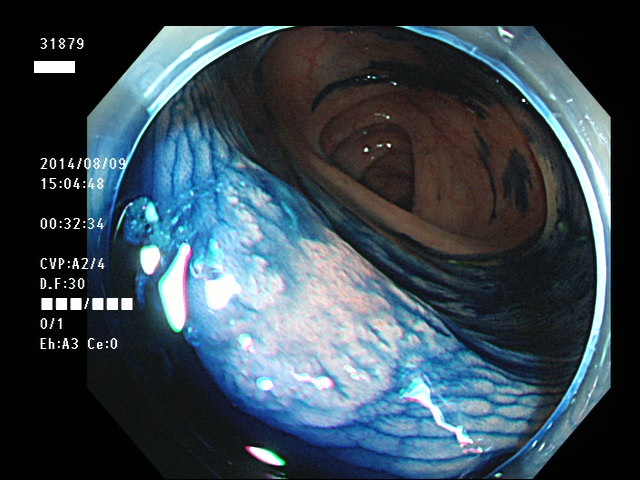

上記100名より抽出した平坦・陥凹型腺腫(=癌化の危険が高いが見落としやすい病変)の内視鏡写真